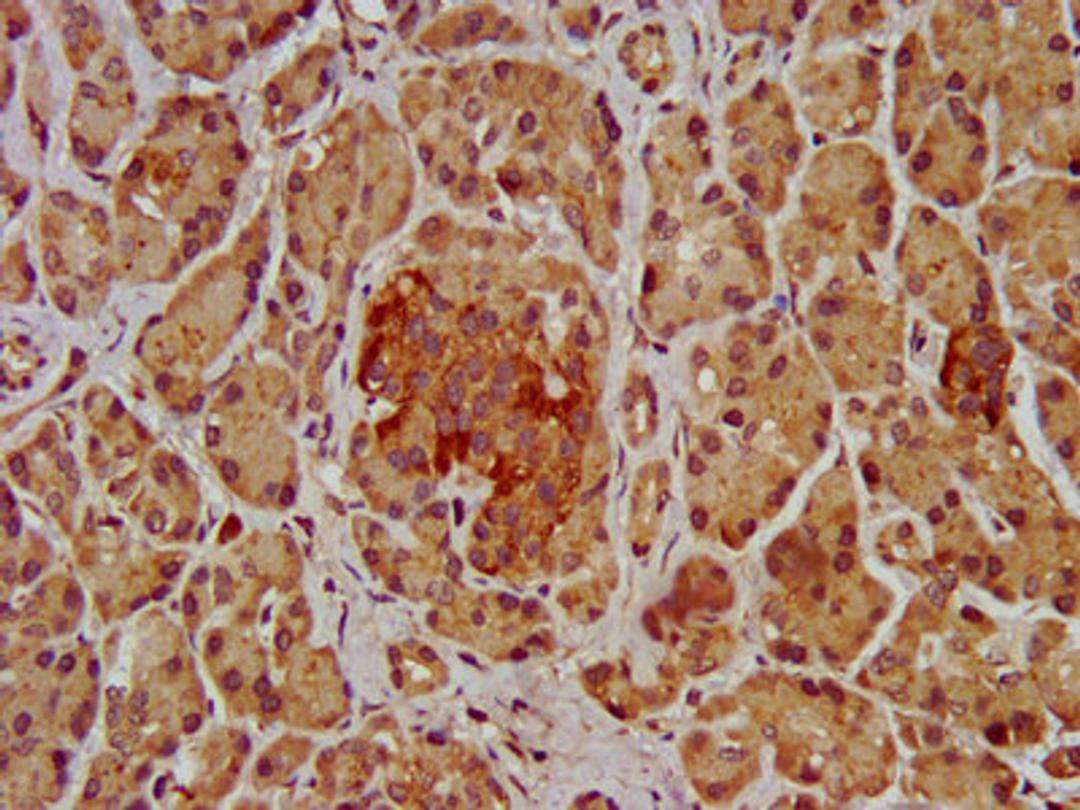

IHC image of CSB-PA622684LA01HU diluted at 1:200 and staining in paraffin-embedded human pancreatic tissue performed on a Leica BondTM system. After dewaxing and hydration, antigen retrieval was mediated by high pressure in a citrate buffer (pH 6.0). Section was blocked with 10% normal goat serum 30min at RT. Then primary antibody (1% BSA) was incubated at 4°C overnight. The primary is detected by a biotinylated secondary antibody and visualized using an HRP conjugated SP system.